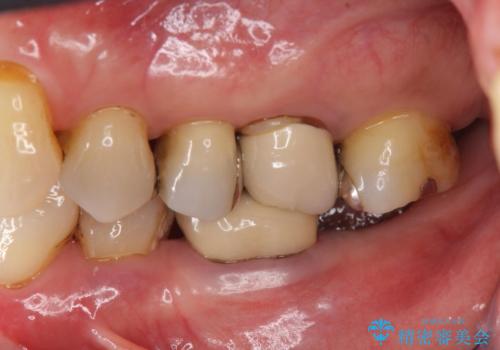

右の奥歯を機能回復|再根管治療とインプラントでしっかり噛める歯へ